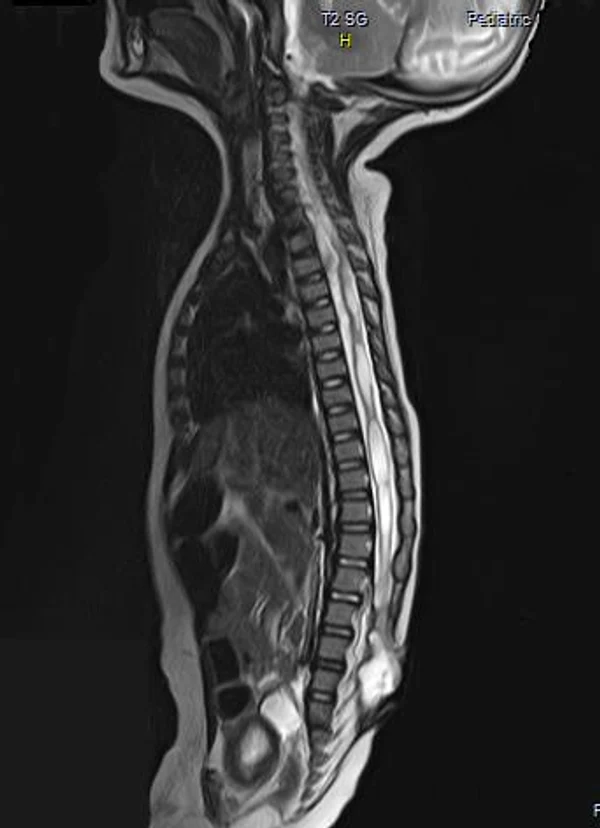

Spina bifida, спинно-мозговые грыжи, диастематомиелия, липоменингомиелолоцеле, фиксированный спинной мозгSpina bifida включают различные типы нарушения закладки и развития нервной трубки на спинальном уровне, что сопровождается незаращением дужек позвоночника и часто сопровождается одновременным пороком развития спинного мозга и его оболочек. Встречаются у 1 на 1000 – 3000 новорожденных. Могут наблюдаться в различных отделах позвоночника, но наиболее часто встречается в пояснично-крестцовом отделе. Незаращение дужек позвонков с наличием грыжевого выпячивания обозначается в литературе по разному: спинно-мозговые грыжи, spina bifida, spina bifida cystica, spina bifida vera, spina bifida typica, spina bifida aperta. Классификация spina bifida aperta: I Рахишизис. II Спинномозговые грыжи. Менингоцеле. Менингорадикулоцеле. Миеломенингоцеле. Миелоцистоцеле. Липоменингомиелоцеле. Основные сопутствующие пороки центральной нервной системы: Гидроцефалия до 65-85%. Аномалия Киари 2. Сирингомиелия.